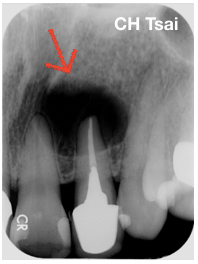

何小姐因左上的側門牙腫脹而來就診,且伴隨著間歇性的抽痛;臨床檢查發現根尖處有輕微壓痛感,放射線檢查後發現根尖有大範圍的破壞(紅色箭頭處)。

經過蔡醫師和何小姐討論後,因為原先牙冠和釘柱的密合度尚可、根管治療的品質也算可以接受,若要重新治療的話必須冒著拆除釘柱過程牙根斷裂的風險,且根尖骨破壞的範圍實在太大,於是決定接受顯微根尖手術。